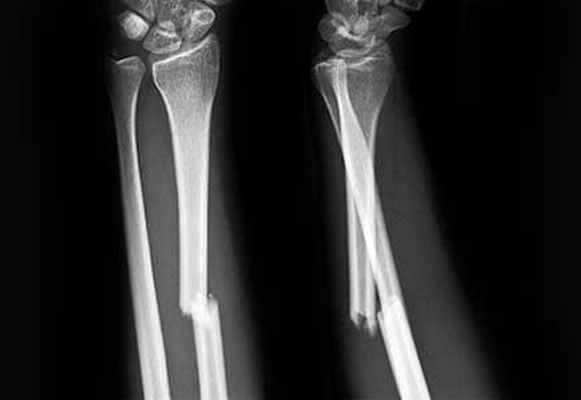

Перелом обеих костей предплечья • Частота — 53% всех переломов костей верхней конечности • Причина: прямая и непрямая травмы • Патоморфология. Характерно сближение отломков лучевой и локтевой кости из-за сокращения межкостной мембраны • Клиническая картина. Больной фиксирует повреждённую руку здоровой рукой. Характерна деформация и укорочение конечности, резкая болезненность при пальпации, осевой нагрузке, сжатии предплечья на удалении от перелома, патологическая подвижность • Лечение •• При переломах без смещения — лонгетно-циркулярная гипсовая повязка в среднем положении предплечья между супинацией и пронацией, тыльном сгибании кисти под углом 25–35° до 8 нед •• При переломах со смещением — одномоментная репозиция ручным способом или с помощью дистракционного аппарата, фиксация гипсовой повязкой на 8–10 нед, чрескостный компрессионно-дистракционный остеосинтез •• При переломах в верхней трети руку иммобилизируют в положении максимальной супинации, в средней трети — в положении полупронации, в нижней трети — вправление в положении пронации, затем переводят в положение полупронации •• Оперативное лечение (остеосинтез) показано при интерпозиции мягких тканей, смещении отломков более чем на половину диаметра, вторичном и угловом смещении костей. Иммобилизация в послеоперационном периоде в положении сгибания предплечья под прямым углом на срок до 10–12 нед.

Переднезадняя и боковая рентгенограммы

Переломы диафизов лучевой и локтевой кости диагностируются с помощью рентгенографии в передне-задней и боковой проекциях. При подозрении на перелом следует также осмотреть локтевой и лучезапястный суставы и, при необходимости, провести рентгенографию.